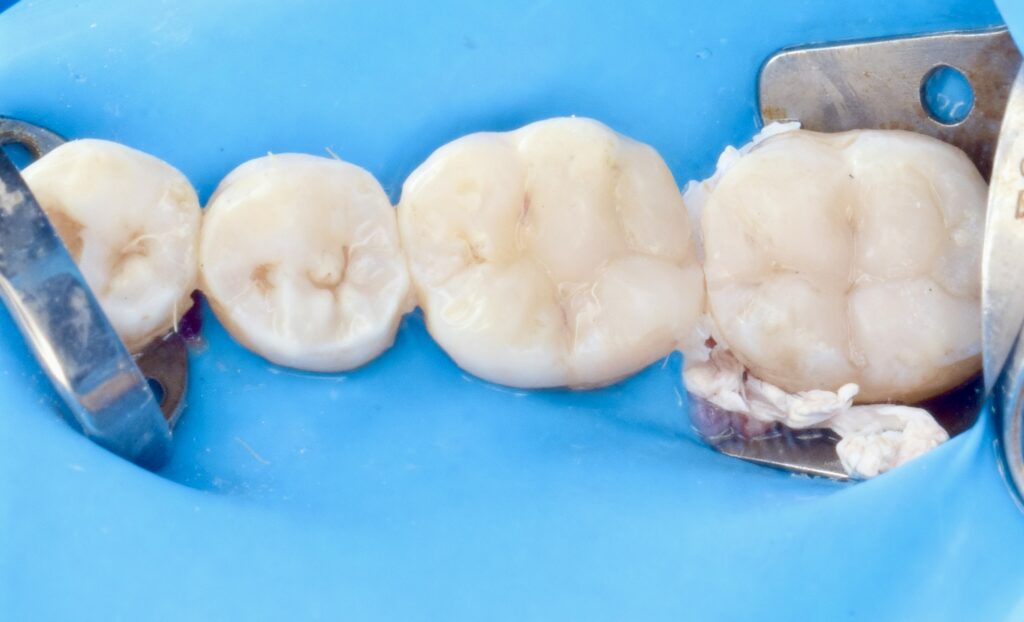

3. Isolation

- Rubber dam applied for moisture control

- Ensured a clean and dry operative field

4. Caries Detection

- Caries detector dye used to highlight infected dentin

- Allowed selective and conservative caries removal